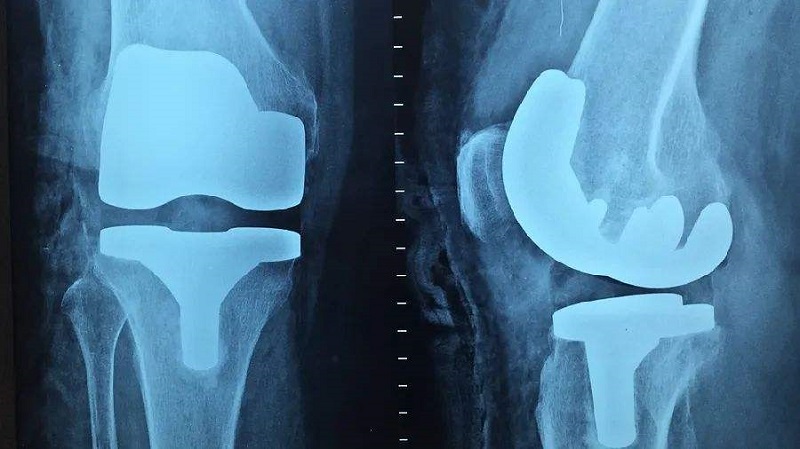

關(guān)節(jié)類植入物產(chǎn)品主要指實(shí)現(xiàn)因關(guān)節(jié)周圍骨折、累計(jì)關(guān)節(jié)的骨腫瘤及其他原因引起的骨缺損等關(guān)節(jié)障礙的關(guān)節(jié)功能重建的人體植入物,主要產(chǎn)品可分為人工膝關(guān)節(jié)、髖關(guān)節(jié)和肩關(guān)節(jié)以及小關(guān)節(jié)等。